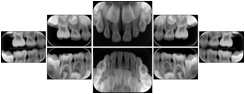

In most standard cases, images are oriented in structured layouts. These structured displays are useful to be shared between providers for reference purposes.

Table OO.1.1-1 shows structured display standard templates, where Viewset ID is based on the Japanese Society for Oral and Maxillofacial Radiology (JSOMR) classification provided by JIRA (Japan Medical Imaging and Radiological Systems Industries Association, www.jira-net.or.jp). Expected or typical teeth to be imaged location, region and designation codes are based on ISO 3950-2010, Dentistry - Designation system for teeth and areas of the oral cavity. For all the hanging protocols listed in OO.1.1-1, the value to use for Hanging Protocol Creator (0072,0008) is "JSOMR" and the value to use for Hanging Protocol Name (0072,0002) does not include "JSOMR" (e.g., "DL-S001A", not "JSOMR DL-S001A").